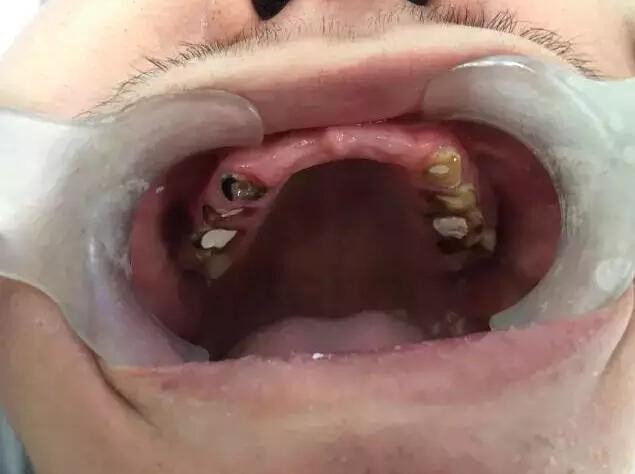

▲浙江一名高中生從小愛喝飲料又不刷牙,牙齒爛光光。(圖/《錢江晚報》)

一位高中生去看牙醫,醫生驚訝地發現,他滿口牙齒已經慘不忍睹。他28顆牙齒拔掉8顆、折斷10顆,剩下的門牙也被腐蝕得很單薄,幾乎變透明。原來,他從小開始就只喝飲料、不喝水,爺爺奶奶寵他,也不太懂口腔保健,所以不會要求他刷牙,他常常嚼口香糖代替刷牙,有時候甚至含著一塊糖睡覺。

章燕珍指出,成年人的口腔裡,有功能的應該有28顆牙齒,上下12顆門牙加上8顆前磨牙以及8顆磨牙,但男孩的這28顆牙齒,其中上門牙6顆、下磨牙2顆因為爛得太徹底,已經不得不拔掉,還有10顆牙齒被飲料腐蝕得脆弱不堪而折斷,甚至齊根折斷與牙齦齊平了。滿口牙齒中,還算「有點樣子」的只剩6顆下門牙,但也被腐蝕得很單薄,牙體幾乎變透明了,基本上只要一咬骨頭,也會馬上碎裂。